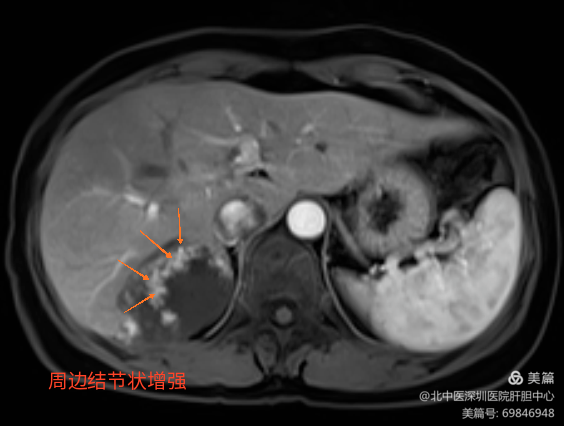

二维MRI图

肝海绵状血管瘤、局灶性结节样增生(FNH)、肝细胞癌的诊断区别